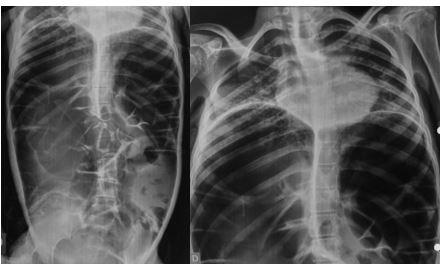

Masculino, 88 anos, aposentado, apresentando quadro demencial leve, assintomático, foi encaminhado ao serviço de endoscopia após a ingestão acidental de sua prótese dentária fixa. O incidente ocorreu há 15 dias, sem eliminação do objeto nas fezes desde então. Ele buscou atendimento na unidade de emergência de sua cidade, onde uma radiografia revelou a presença do objeto na topografia da fossa ilíaca direita (foto 1). Ao exame físico, não havia alterações relevantes com palpação do abdome inocente.

Após preparo colônico com manitol e a realização de uma nova radiografia, que não apontou qualquer mudança na posição inicial da prótese dentária desde a admissão, o paciente foi submetido a colonoscopia. Até a intubação cecal o corpo estranho não foi encontrado, com presença de doença diverticular no hemicólon esquerdo (foto 2 e 3).